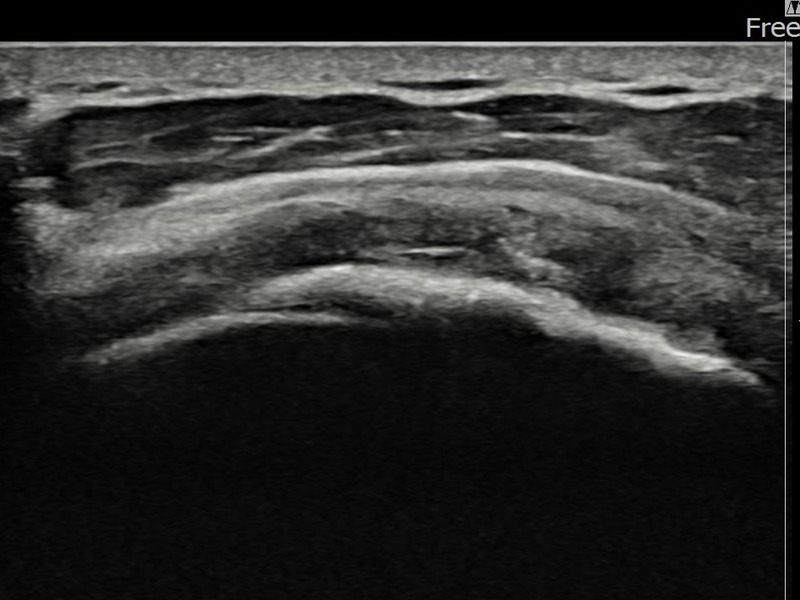

김ㅇㅇ님 · 좌측 극상근건 광범위 부분파열

좌측 어깨 광범위 파열로 수술을 권유받았으나 비수술 치료를 원해 내원하셨습니다. 초음파 검사에서 극상근건 전층에 걸친 광범위 부분파열이 확인되었으며, 어깨인대 축소봉합술 후 구조적 안정화와 기능 회복이 이루어졌습니다.